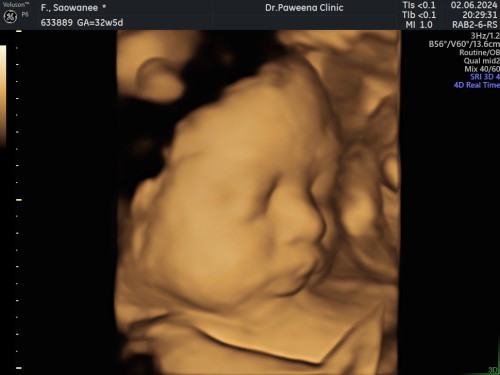

สาวน้อยได้กลับมาอีกครั้ง

ใช้เวลา2ปี ทำicsi2ครั้งไม่ติด ติดครั้งที่3หลังทำprpรังไข่😍

แก้มมาเต็มเลยค่ะสาวน้อย